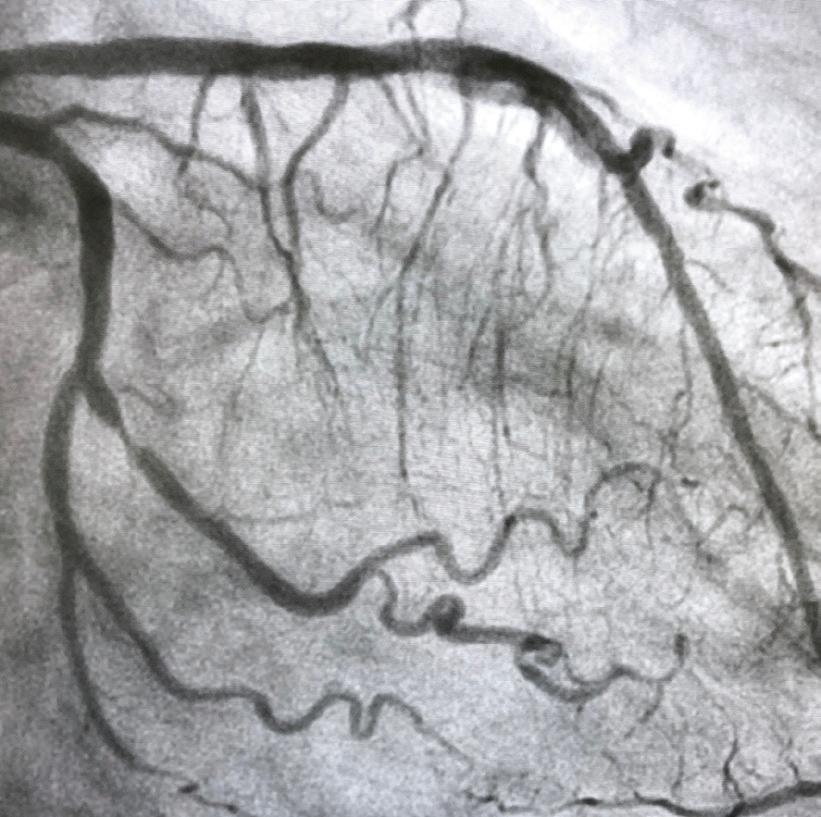

Infarkt miokarda